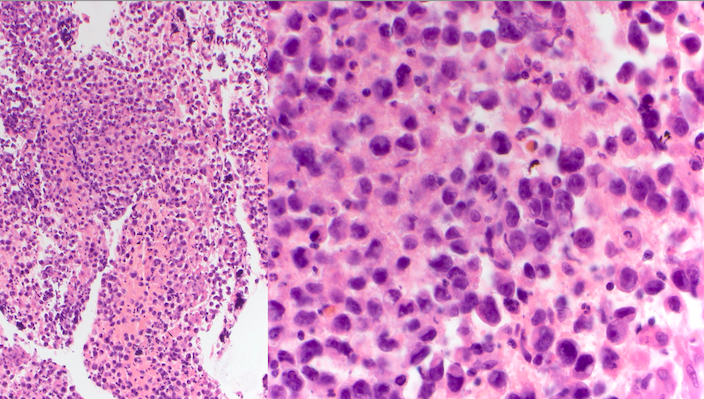

The specimen is cellular and consists of abundant large and dyshesive cells with somewhat rhabdoid/plasmacytoid morphology, prominent nucleoli, and moderate amounts of vacuolated cytoplasm. In the background there are small lymphocytes and a focal bubbly/tigroid appearance, as well as non-necrotizing granulomas.

Immunohistochemical stains were performed on this case. The cells were positive for OCT3/4 and SALL4, and negative for cytokeratin cocktail, SOX10, INI1 (retained), and SMARCA4 (retained). Together with the morphology, this staining pattern is consistent with germ cell neoplasm.

Germ cell tumors (GCTs) are classified as extragonadal if there is no evidence of a primary tumor in the testes or ovaries. Extragonadal GCTs typically arise in midline locations; in adults, the most common sites, in order of frequency, are the anterior mediastinum, the retroperitoneum, and the pineal and suprasellar regions. Based on morphology, they are typically divided into seminomas versus nonseminomatous GCTs (teratomas [mature or immature], embryonal carcinomas, yolk sac tumors and choriocarcinoma) The two key issues in establishing the diagnosis are the exclusion of metastasis from a primary testicular GCT and distinguishing from another type of poorly differentiated tumor. This patient underwent a subsequent radical orchiectomy that showed testicular parenchyma with marked tubular atrophy, hyalinosis, scarring, focal dystrophic calcifications, hemorrhage, Sertoli cell adenomas, and hyperplastic Leydig cells, suggestive of regressed germ cell tumor.